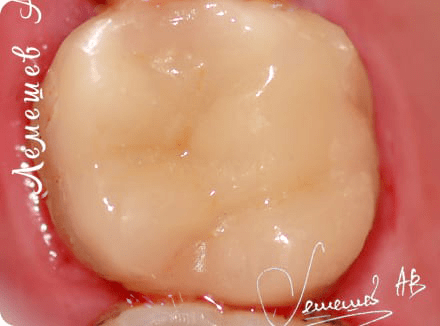

Установка керамической коронки

Доктор: Лемешев Алексей Валерьевич